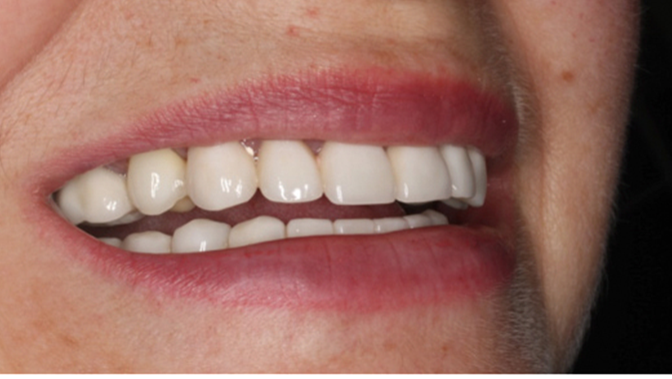

“Patient’s smile was recovered on the day of surgery

with reliable & highly-aesthetic results using AnyRidge & R2GATE. ”